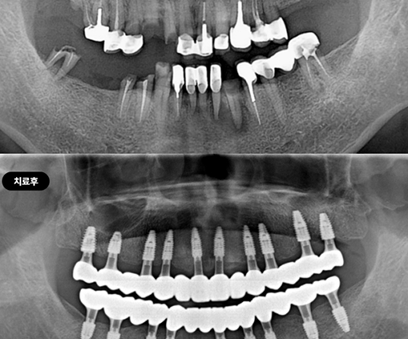

Вторичная имплантация: даём второй шанс

Не каждая клиника готова качественно справиться с полной реконструкцией зубного ряда. Это сложная операция, требующая системного подхода.

В нашей клинике используется цифровая система планирования, что позволяет точно спланировать место установки каждого импланта, минимизировать хирургическое вмешательство и сразу же установить индивидуальные протезы.